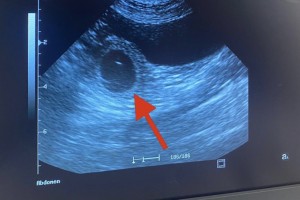

Unsere Annie ist trächtig 🙂 Wir

Die Babies in Annie’s Bäuchlein sind nun ca. 2,5 cm groß. Die männlichen und weiblichen Sexualhormone werden sichtbar und die